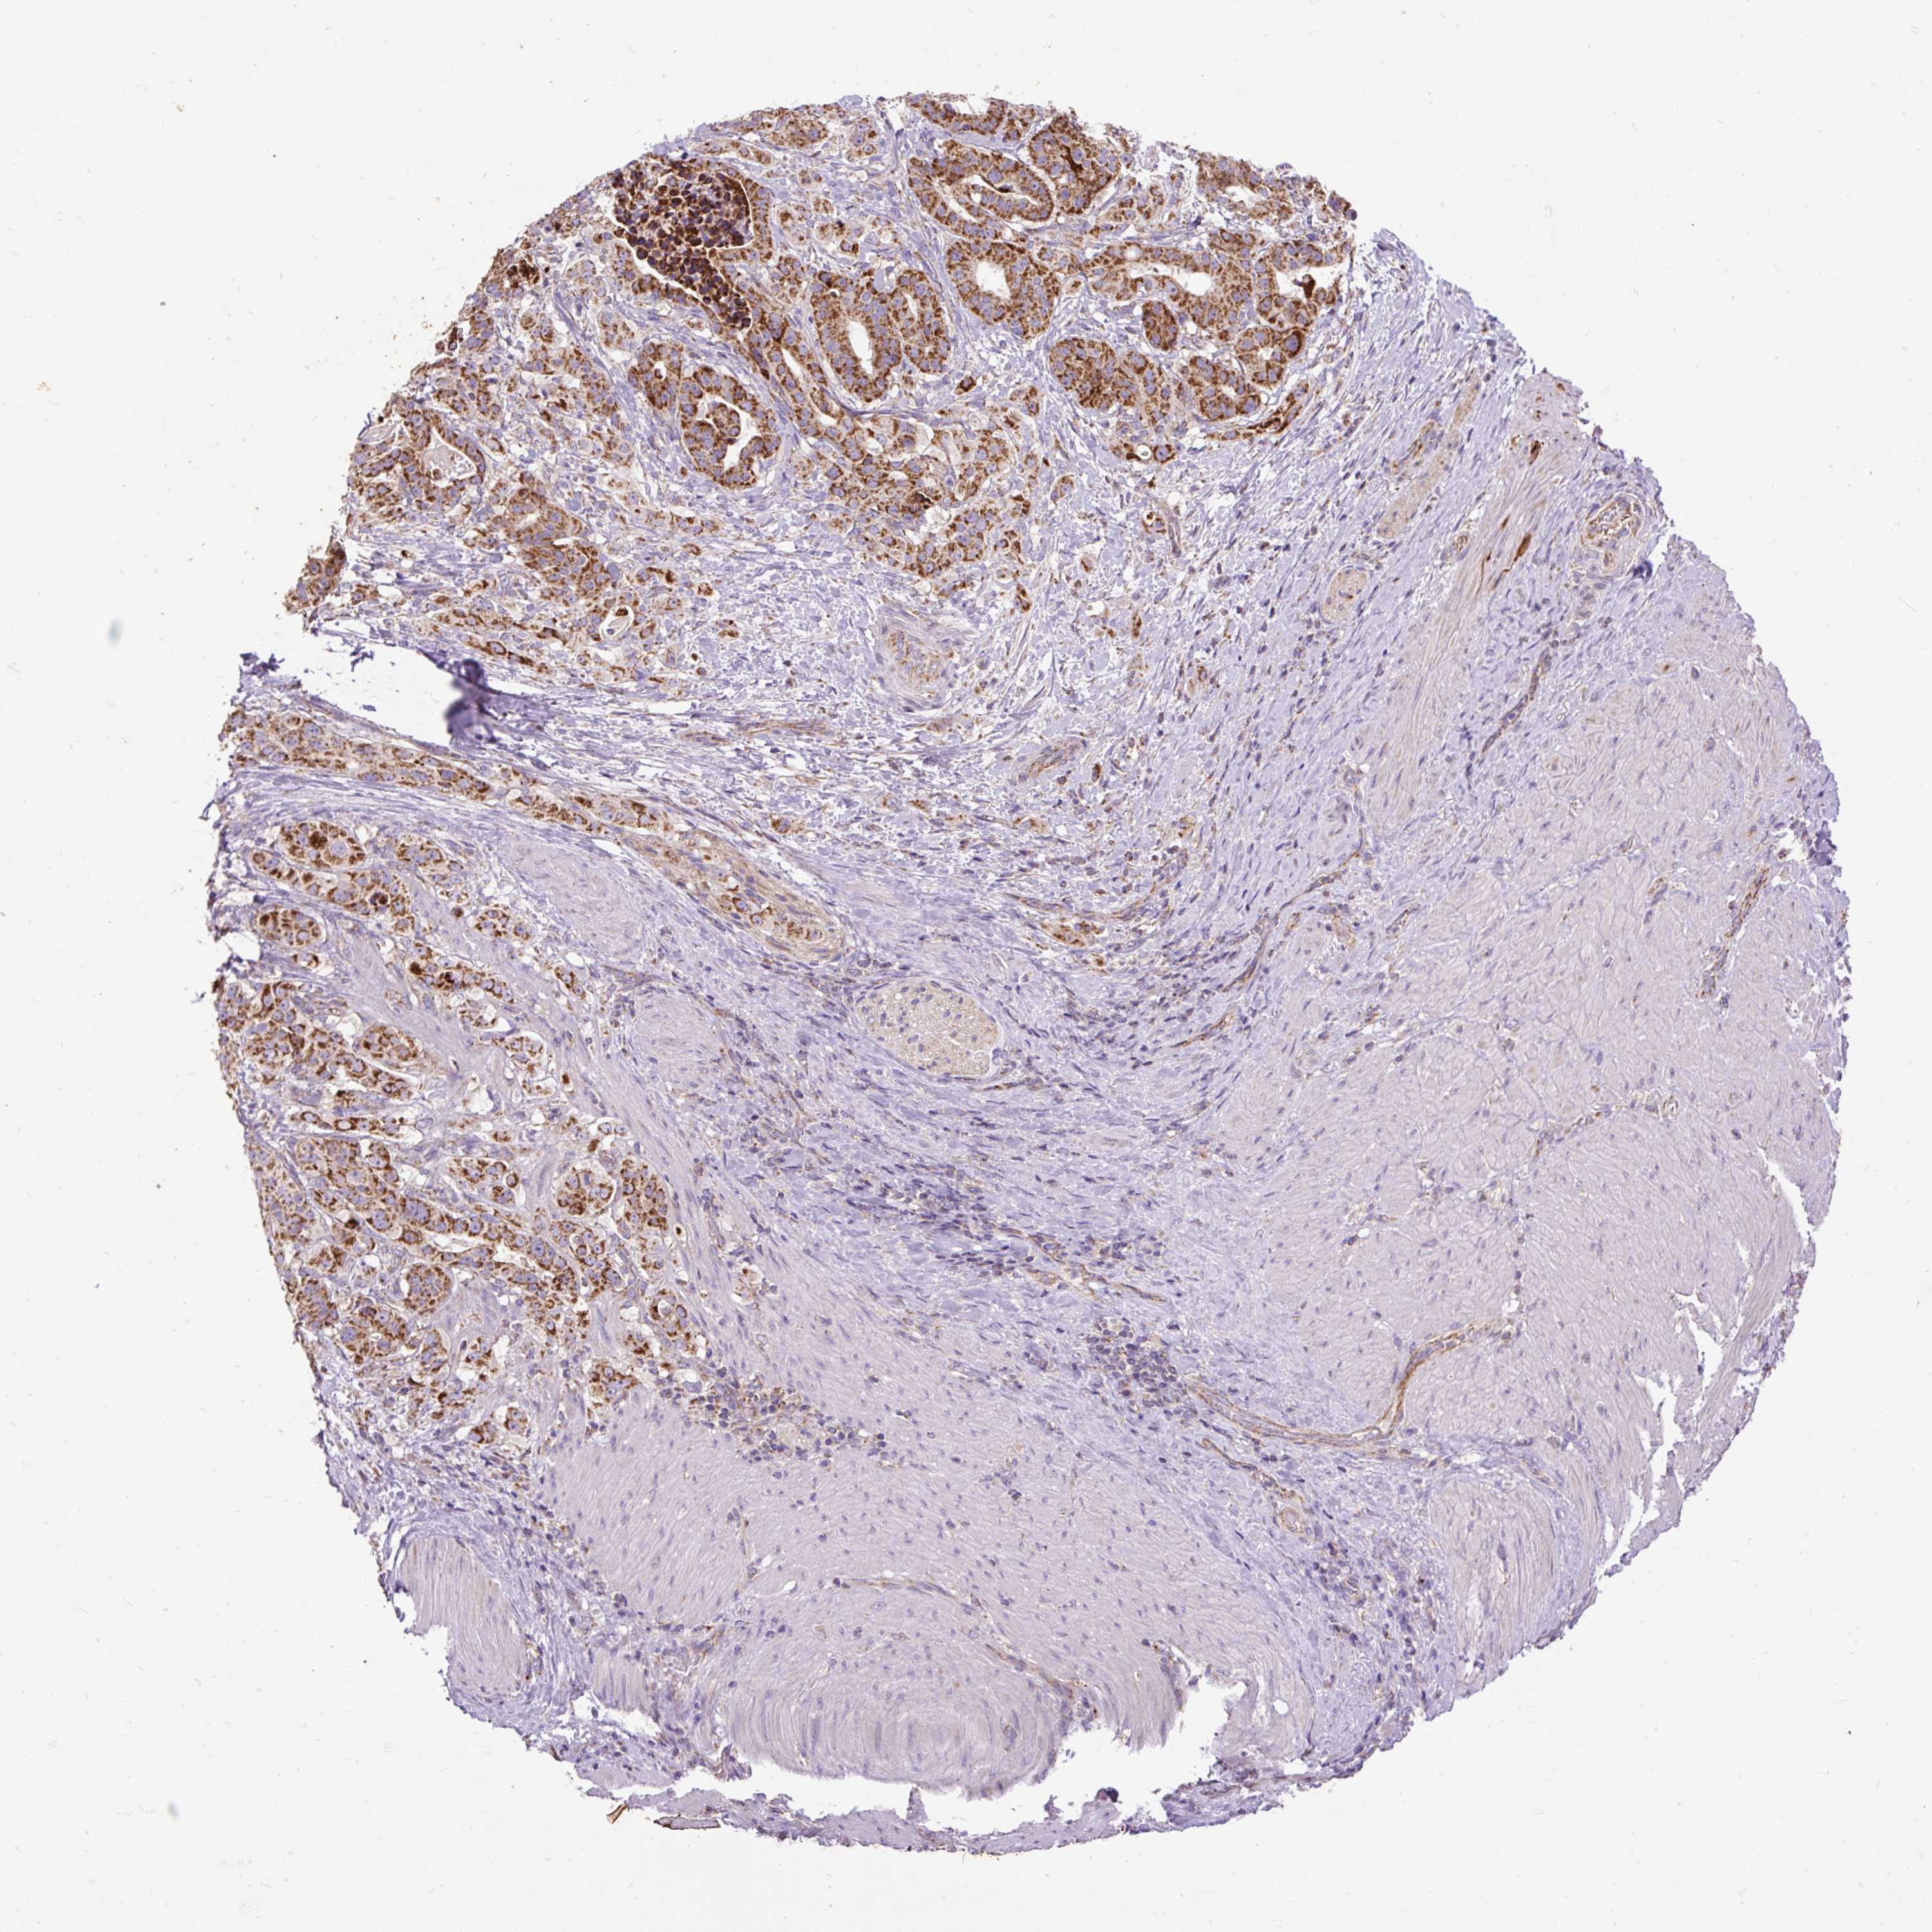

STOMACH CANCER - Protein expressioni

A mouse-over function shows sample information and annotation data. Click on an image to view it in a full screen mode. Samples can be filtered based on level of antibody staining by selecting one or several of the following categories: high, medium, low and not detected. The assay and annotation is described here.

Note that samples used for immunohistochemistry by the Human Protein Atlas do not correspond to samples in the TCGA dataset.

Antibody stainingi

Antibody staining in the annotated cell types in the current human tissue is reported as not detected, low, medium, or high, based on conventional immunohistochemistry profiling in selected tissues. This score is based on the combination of the staining intensity and fraction of stained cells.

Each image is clickable and will lead to virtual microscopy that enables deeper exploration of all samples and also displays staining intensity scores, fraction scores and subcellular localization as well as patient and tissue information for each sample.

Antibody HPA036231

Antibody HPA036232

Staining

High

Medium

Low

Not detected

Intensity

Strong

Moderate

Weak

Negative

Quantity

>75%

75%-25%

<25%

None

Location

Nuclear

Cytoplasmic/membranous

Cytoplasmic/membranous,nuclear

Adenocarcinoma, NOS